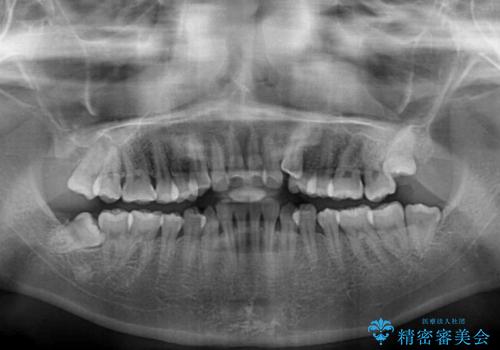

- 八重歯と前歯のデコボコを気にして来院された患者様です。

八重歯の他に、上顎歯列を狭窄しているという問題点がありました。

また、八重歯により上顎奥歯が前方に位置しており、咬み合わせの改善も必要な状況でした。

インビザラインによる矯正治療を希望されたため、上顎歯列の側方拡大奥歯の遠心移動のための補助装置を併用し、その後はインビザラインにて行うこととしました。